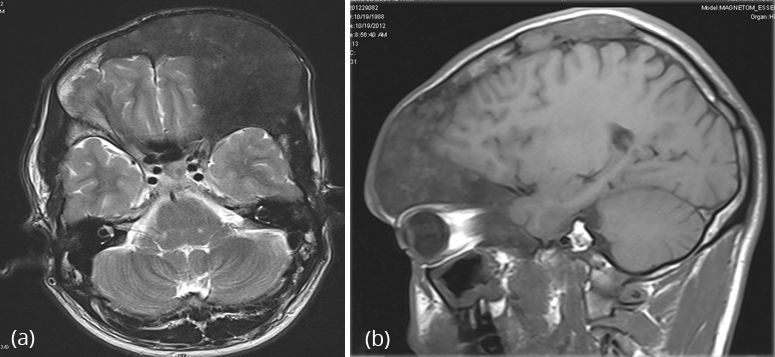

MRI – (Figure 25a,b,c)

MRI is not particularly useful in differentiating fibrous dysplasia from other entities as there is marked variability in the appearance of the bone lesions, and they can often resemble tumour or more aggressive lesions.

On T1-weighted images, the signal intensity is usually low to intermediate, depending on the ratio of fibrous tissue to mineralized matrix. Lesions with high fibrous tissue content tend to have intermediate signal intensities, whereas lesions with highly mineralized stroma tend to show lower signal intensities. On T2-weighted images, the MR signal intensities are more variable. Some lesions with a highly mineralized matrix show correspondingly low signal intensities, whereas lesions with high fibrous tissue content and cystic spaces return high signal intensities (Figure 26a,b).

Heterogeneous enhancement after administration of gadolinium is noted.

Figure 26a,b: FD MRI – Axial and lateral sections.